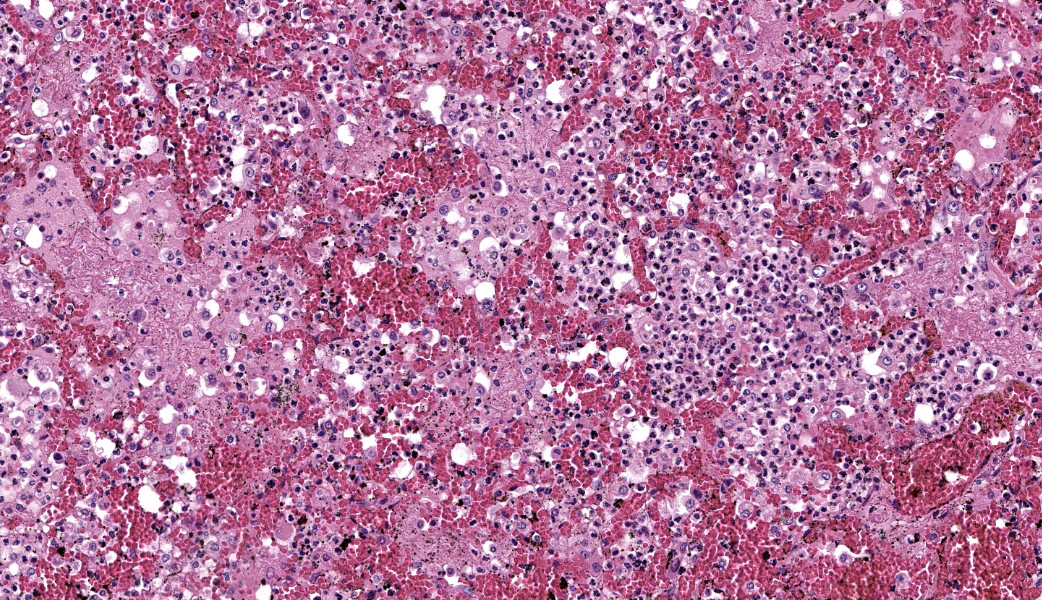

Typical pathological changes in equids with viral pneumonia include pulmonary consolidation in a lobular pattern separated by unaffected or overinflated lung lobules, or less commonly, a diffuse pattern of pneumonia.1 EIV infections complicated by secondary bacterial infections are characterized by fibrinosuppurative exudate and pulmonary consolidation, mostly restricted to the cranioventral pulmonary lobes (bronchopneumonia).1,12,13 Histopathologically, acute stages typically reveal rhinitis and tracheitis with epithelial necrosis and infiltrates of lymphocytes in the lamina propria. Subacute to chronic lesions consist of epithelial hyperplasia and squamous metaplasia.6,11 Affected lungs exhibit bronchointerstitial pneumonia with hyaline membranes in the alveoli, type II pneumocyte hyperplasia, and necrotizing bronchitis/bronchiolitis. Secondary bacterial bronchopneumonia may also develop.4,6,12

Lung: Pneumonia, bronchointerstitial, necrotizing and fibrinosuppurative, acute, multifocal to coalescing, marked, with thrombosis, edema, and hyaline membranes.

Determining differentials in a case of viral pneumonia in any species requires a working knowledge of viral pathogenesis and target cells to refine the list of potential offenders. In this case, the most striking hallmarks for influenza virus include the end-airway epithelial necrosis and patchy areas of hemorrhage. Influenza is both endotheliotropic and epitheliotropic and, while it affects epithelial cells in the upper airways, it has unique tropism for the type I and type II pneumocytes of the alveoli as well. It causes significant destruction to end-airways as a result. This key difference can help separate an influenza infection from other pneumotropic viruses, such as calicivirus in cats. (Feline calicivirus infection of the lung can look nearly identical to an H5N1 influenza virus infection in a cat, but the state of the end airways can help clue in the pathologist to which virus is most likely and can assist in decision-making for next testing steps. The more virulent strains of feline calicivirus can cause severe interstitial pneumonia, but they do not cause necrosis of end airways the way that influenza does.)